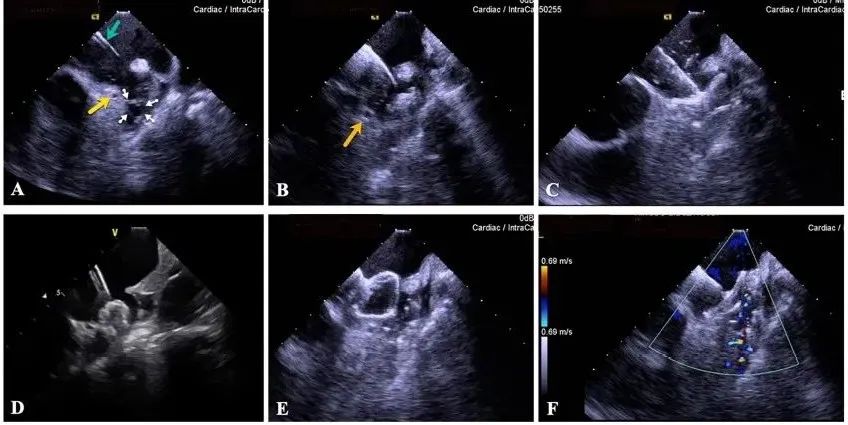

一種與心導(dǎo)管檢查相結(jié)合的超聲心動(dòng)圖診斷新興技術(shù),通過將超聲探頭置于心腔內(nèi)部,發(fā)射并接收超聲信號,來精確獲取心臟解剖結(jié)構(gòu)、心臟血流動(dòng)力學(xué)等信息的實(shí)時(shí)成像。與其他影像技術(shù)相比,ICE技術(shù)具有操作簡單、無輻射、安全性高、手術(shù)效率高、實(shí)用等優(yōu)勢,ICE在很大程度上有望取代經(jīng)食道超聲心動(dòng)圖(TEE),成為電生理和結(jié)構(gòu)性心臟病領(lǐng)域的理想成像方式。

目前ICE技術(shù)已被應(yīng)用于左心耳封堵、房顫射頻消融、二尖瓣成形、房間隔缺損封堵等多種心臟介入手術(shù),應(yīng)用場景主要圍繞心臟電生理、結(jié)構(gòu)性心臟病等領(lǐng)域,目前以電生理應(yīng)用為主。數(shù)據(jù)顯示,我國結(jié)構(gòu)性心臟病介入器械市場規(guī)模已從2017年的4億元增長至2021年的20億元,年復(fù)合增長率達(dá)48.3%;預(yù)計(jì)到2025年,該市場規(guī)模將達(dá)到104億元,可以預(yù)見ICE市場規(guī)模也將同步高速增長,未來市場發(fā)展空間廣闊。

心腔內(nèi)超聲(ICE)技術(shù)壁壘極高,國內(nèi)主要廠商核心部件仍舊為進(jìn)口,集成了超聲和圖像處理最前端技術(shù),包括超聲探頭、線纜、軟件成像算法等,是當(dāng)前內(nèi)窺超聲方向最具挑戰(zhàn)的領(lǐng)域。ICE的應(yīng)用經(jīng)歷了2D平面成像、3D三維立體成像、以及4D的實(shí)時(shí)三維立體成像階段。